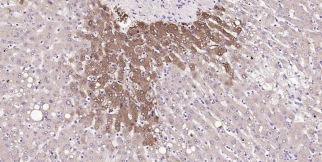

Immunohistochemical analysis of paraffin embedded human liver tissue slide using IHC0333H (Human Glutamine synthetase Kit).

Human Glutamine synthetase Ready-To-Use IHC Kit